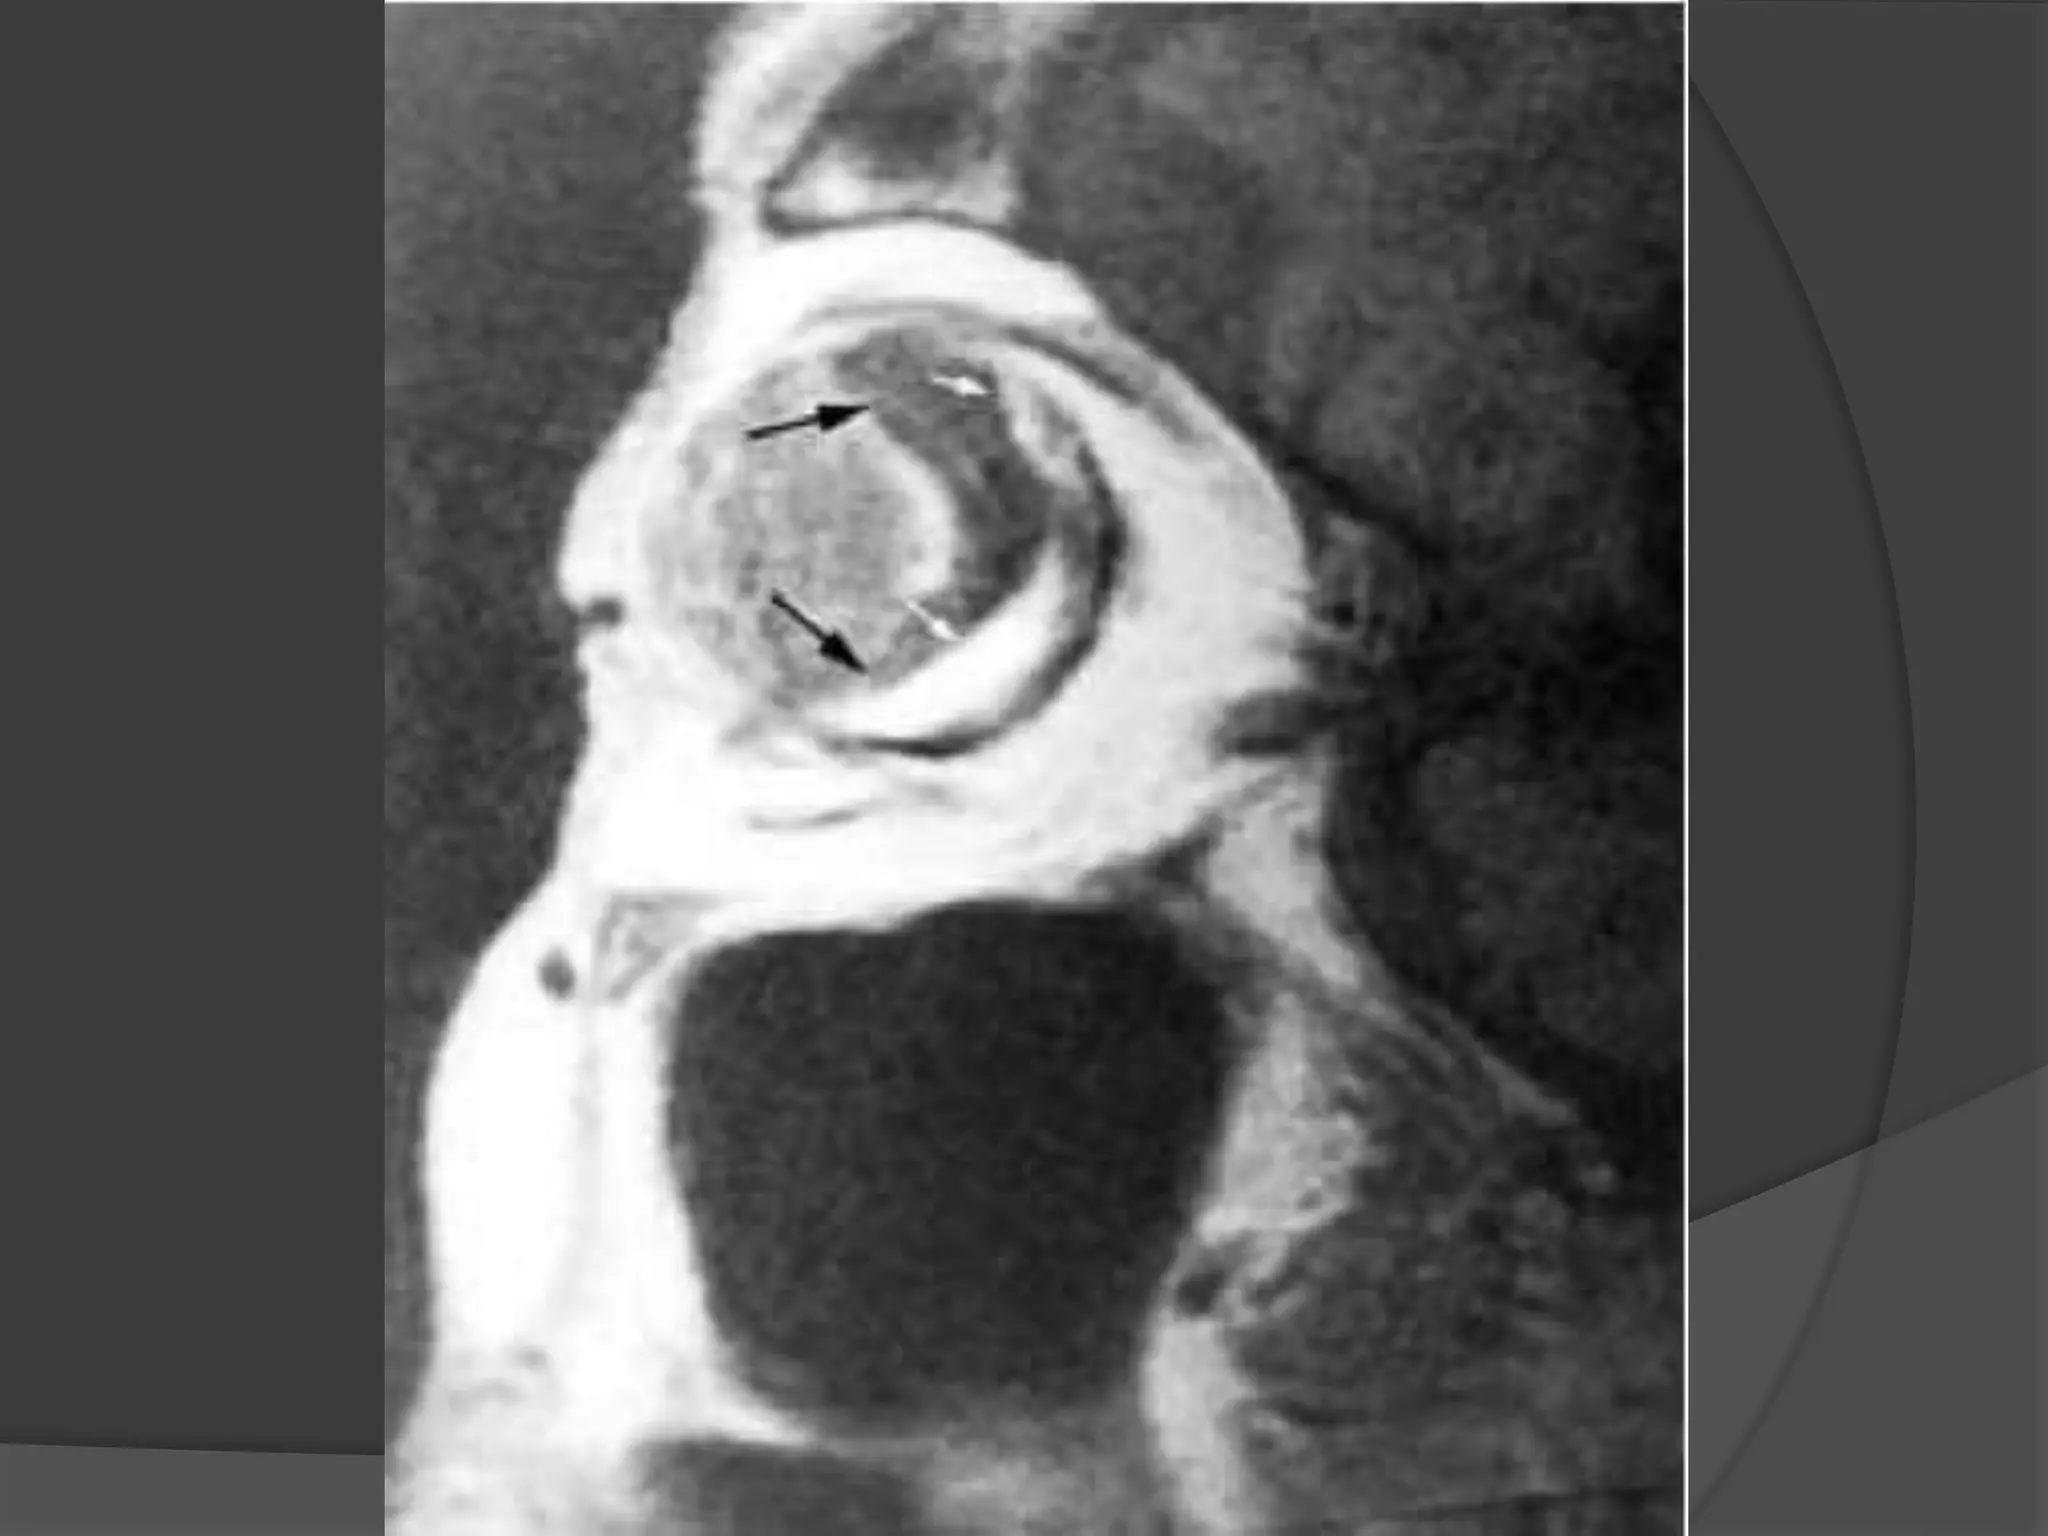

Fig A. Optic nerve Meningiomas. CT -- Enhancement of thickened right

optic nerve with elevation of optic disc (arrowhead).

Fig B. Axial T1-weighted post contrast fat-saturated image (B) demonstrates

peripheral enhancement of the thickened right optic nerve sheath.

Nonenhancing soft tissue within represents the encased optic nerve.

Fig A. Opticnerve Meningiomas. CT -- Enhancement of thickened right optic nerve with elevation of optic disc (arrowhead). Fig B. Axial T1-weighted post contrast fat-saturated image (B) demonstrates peripheral enhancement of the thickened right optic nerve sheath. Nonenhancing soft tissue within represents the encased optic nerve.